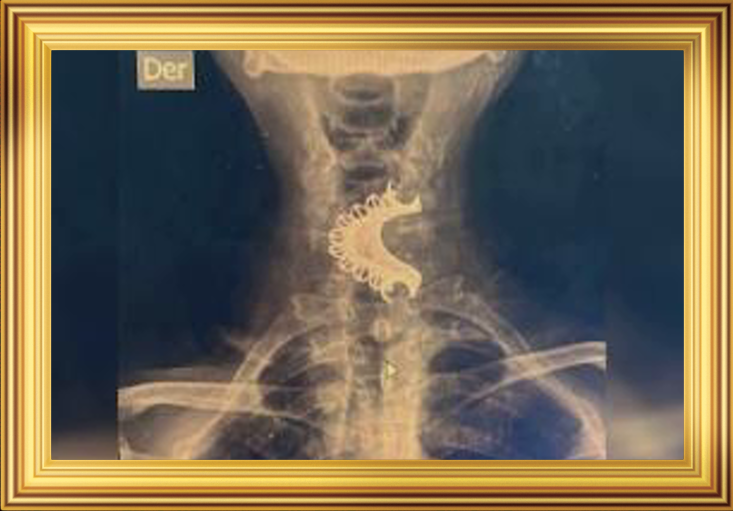

Когда наконец-то Хулиан решился на визит в больницу, рентген показал то, что все ожидали увидеть: в его горле уютно расположился зубной протез. Это было похоже на то, как если бы вы нашли в холодильнике забытый пирог:

Пациента перевели в специализированную клинику для удаления инородного тела. Гастроэнтеролог с энтузиазмом взялся за операцию, словно это была последняя миссия на Земле. И вот, после успешной процедуры, Хулиан выписался из больницы с новыми перспективами — и без протеза.